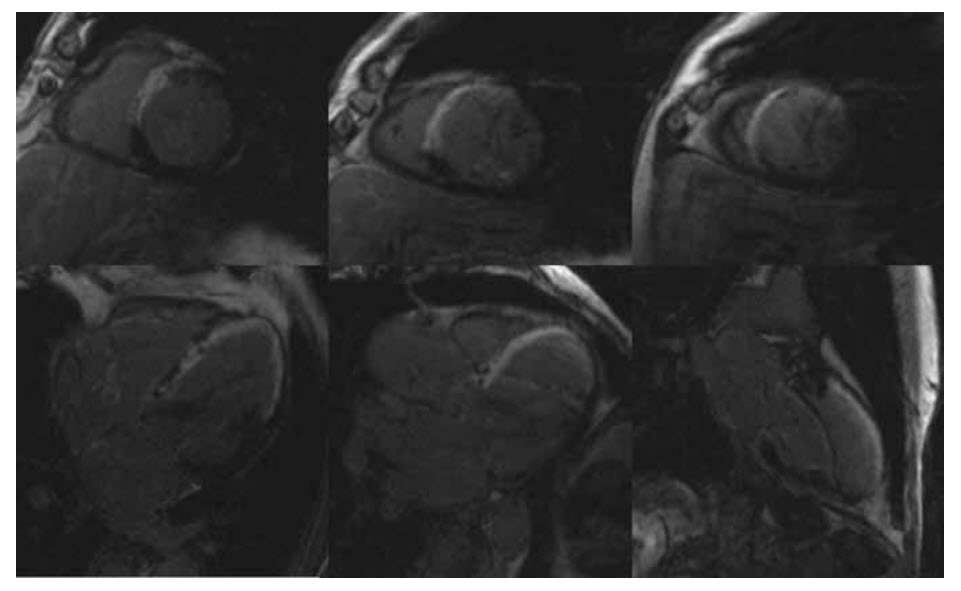

A 73-year-old male presents with breathlessness on exertion. His current medication consists only of amlodipine 5 mg od. His ECG demonstrates voltage criteria for left ventricular hypertrophy. A TTE reveals LVH so he is referred for CMR. Video below shows the long-axis cines

and Video below shows the short-axis cines.

Figure below shows the late myocardial enhancement of the four-, three-, and two-chamber views (top row, left to right) and the short-axis views at the basal, mid, and apical levels (bottom row, left to right).

What is the most likely diagnosis?

A. hypertrophic cardiomyopathy

B. amyloid

C. hypertensive heart disease

D. Fabry’s disease

E. None of the above